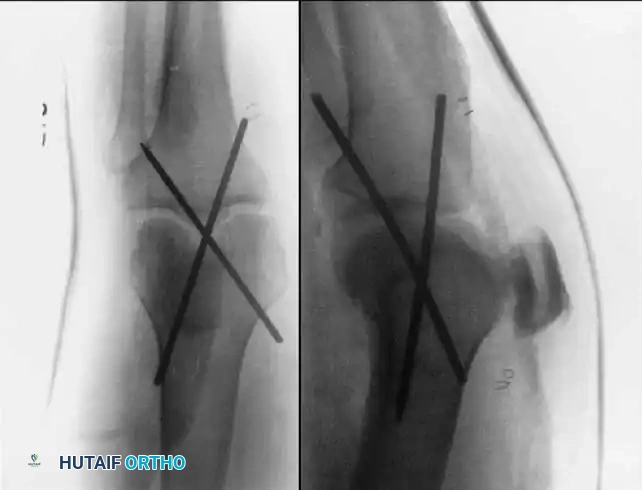

Historically, transarticular pins were driven from the anterior eminence of the tibia into the femur to provide immediate stability.

KNEE Surgical Diagram

While effective for rigid immobilization, transarticular pins have been associated with significant complications, including pin track infection, septic arthritis, and pin breakage. Therefore, they should be used with extreme caution. We have found a transarticular pin to be uniquely useful when the posterior capsule is completely disrupted, preventing concentric reduction in full extension. In such specific cases, the pin is left in place for 4 to 6 weeks, after which it is removed, and range of motion is initiated.